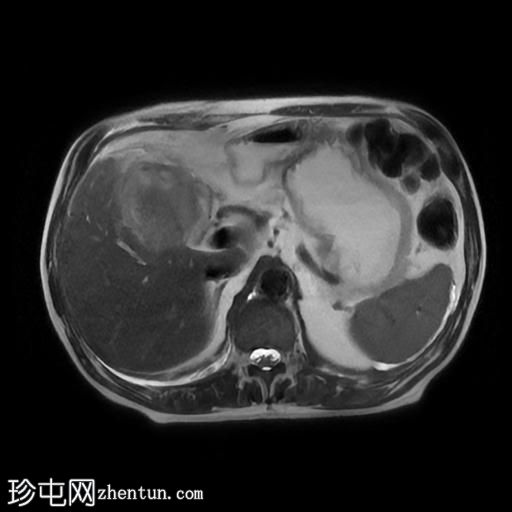

胆囊切除术后十天出现剧烈腹痛,伴恶心呕吐。

年龄:75岁

性别:男

MRI

轴位T2加权像

胆囊切除术后,可见肝总管局部断裂,尤其是在胆囊管开口上方。该断裂伴有胆囊切除部位形成较大的血肿或胆汁瘤。

胆管损伤可能发生在手术过程中,导致胆汁渗漏到周围组织,从而形成血肿或胆汁瘤。这可能出现明显的临床症状,并可能需要进一步干预,具体取决于病情的严重程度和患者的临床表现。